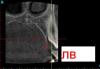

kriokov Опубликовано 1 июля, 2012 Поделиться Опубликовано 1 июля, 2012 (изменено) скачал кт, чудес у пациентки хватает. Резорбция 21 большая с переходом на боковой периодонт с медиальной поверхности ( может от туда и начинался процесс), + ретенированный клык справа , коронка вестибулярно и фолликулярная (зубосодержащая) киста вокруг его коронки, чего с 21 делать не знаю, (удалять скорее всего), а клык несмотря на кистозное образование надо вытаскивать в зубную дугу.по поводу диагноза 21- только предположительно МКБ -10 К03-3 патологическая резорбция зуба Изменено 1 июля, 2012 пользователем kriokov Ссылка на комментарий

kriokov Опубликовано 1 июля, 2012 Поделиться Опубликовано 1 июля, 2012 насчет ретинированного клыка-- может я погарячился, так как в инфо на кт возраста пациентки не нашел, может он просто в стадии прорезывания Ссылка на комментарий

kriokov Опубликовано 1 июля, 2012 Поделиться Опубликовано 1 июля, 2012 на панораме так выглядет Ссылка на комментарий

zybnaya feya Опубликовано 1 июля, 2012 Автор Поделиться Опубликовано 1 июля, 2012 насчет ретинированного клыка-- может я погарячился, так как в инфо на кт возраста пациентки не нашел, может он просто в стадии прорезывания Он в стадии прорезывания) Не пугайте))) Девочке 10-11 лет,я точно не помню Ссылка на комментарий